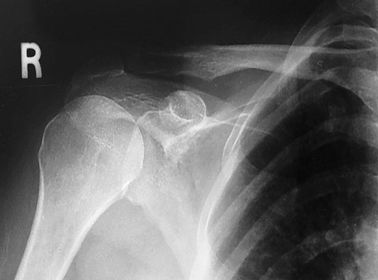

Which projections/positions are these? (top->bottom) TOP: Scapular Y-View _________________________ BOTTOM: AP External Rotation (greater tubercle in profile)